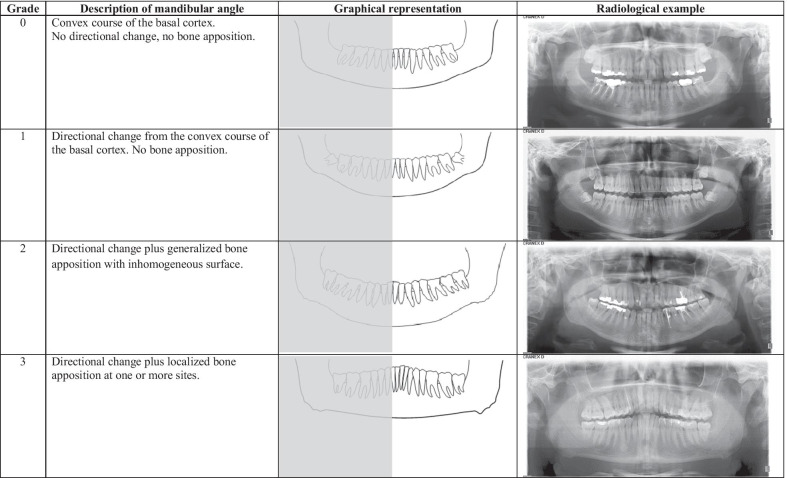

Chewing will cause bone apposition on gonions (wider jaw), won't lengthen ramus. Clenching will lengthen ramus. Do clenching (lightly).

12903 2021 1804 Fig1 HTML